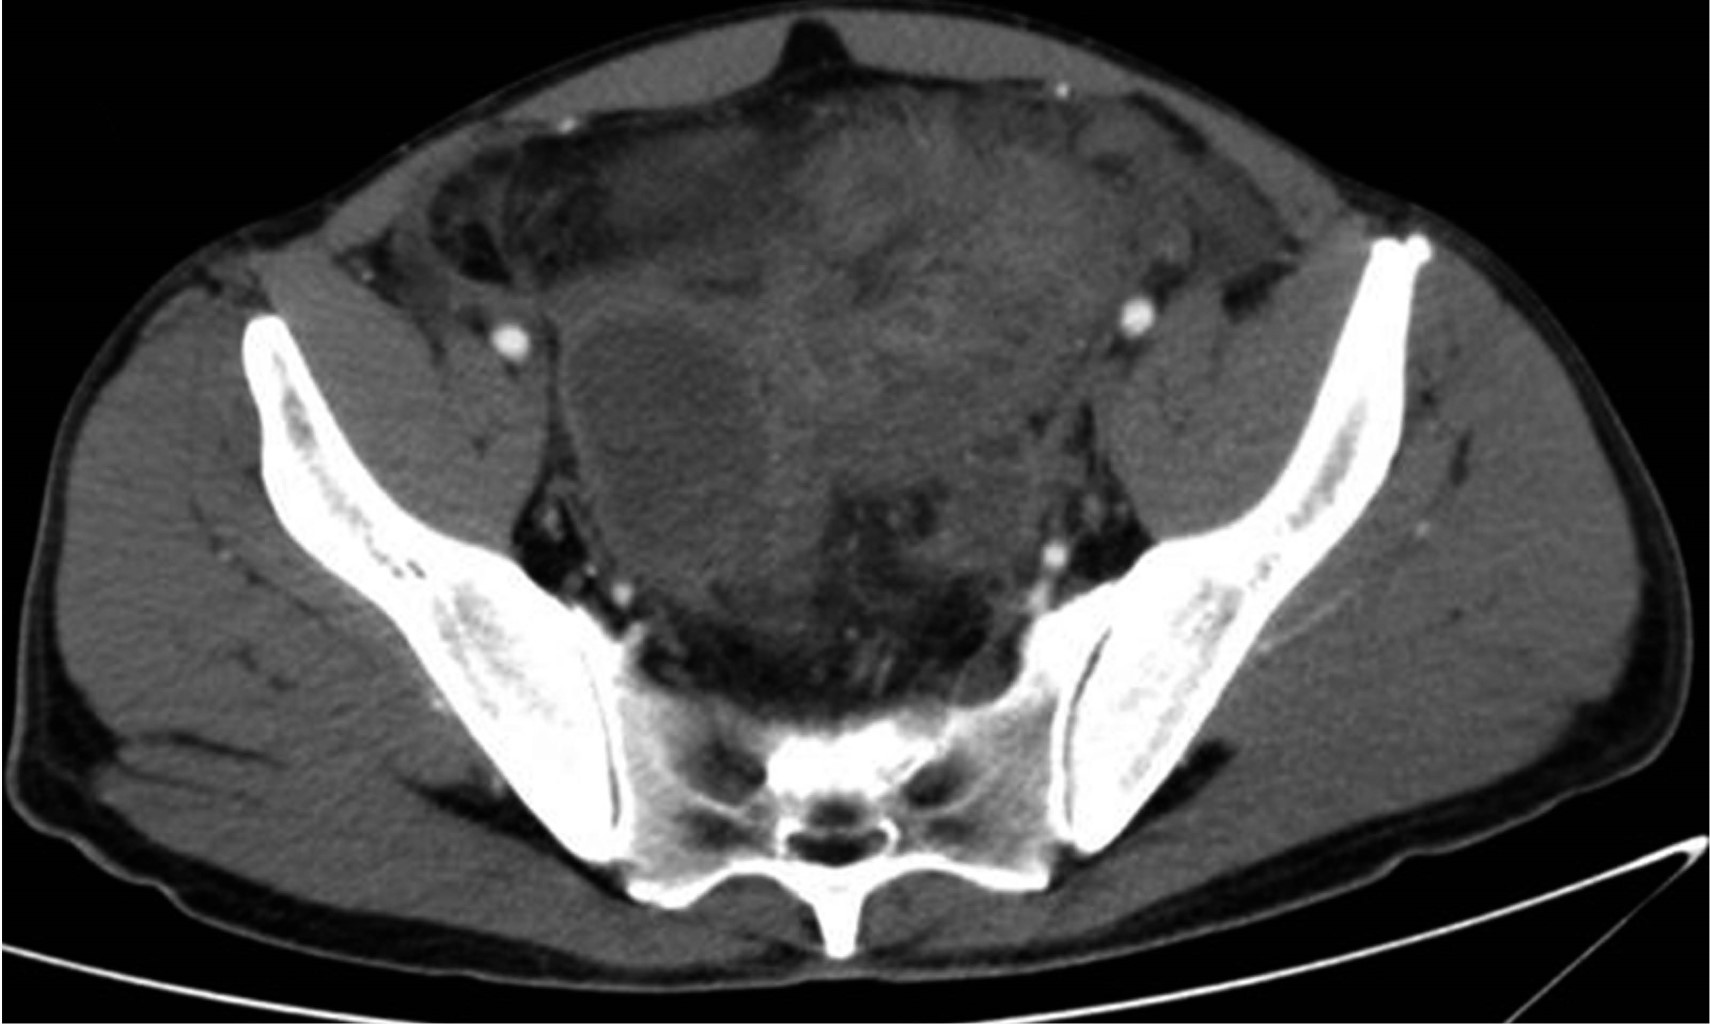

La tomografía de abdomen y pelvis con contraste iv demostró líquido libre en corredera parietocólica derecha, interasa y pericecal. Apéndice cecal con diámetro de 14 mm además de engrosamiento y realce de su pared. Colección supravesical con extensión a fosa iliaca derecha que mide 55 × 75 × 41 mm con un volumen calculado de 88 cm3 (Figura 1) y otra en fondo de saco con extensión a fosa iliaca izquierda que mide 60 × 57 × 70 mm con volumen de 125 cm3. Se decidió punción guiada por ultrasonido con control tomográfico de ambas colecciones (Figura 2), drenando 70 y 120 cm3 purulentos respectivamente. Se dejaron dos drenajes tipo Dawson Mueller® 10.2 fr, uno en fosa iliaca derecha y otro en fondo de saco. Se inició manejo antimicrobiano de amplio espectro con meropenem 1 g iv cada ocho horas y vancomicina 1 g iv cada 12 horas, se dejó en ayuno dos días y se inició apoyo nutricional parenteral durante tres días con oliclinomel®. El cultivo aeróbico desarrolló Streptococcus constellatus sensible a ertapenem, por lo que se cambió cobertura antimicrobiana a base de ertapenem 1 g iv cada 24 horas y vancomicina. El paciente se mantuvo clínicamente estable, sin datos de respuesta inflamatoria sistémica y disminución progresiva del dolor abdominal. Una TAC de control en su tercer día (Figura 3) demostró una disminución importante del líquido en el interior de las colecciones. Se retiró el drenaje derecho en su cuarto día, con un gasto total de 10 cm3; los marcadores inflamatorios presentaron una disminución progresiva durante su estancia, egresándose con 9.9 10^3/μl leucocitos, seg 67%, bandas 0 % y PCR 4.05 mg/dl. Se retiró el drenaje izquierdo previo a su egreso en el noveno día de estancia con un gasto total de 82 cm3. No se realizó apendicectomía de intervalo en el seguimiento debido a que, basado en la edad, los antecedentes y los estudios de imagen al diagnóstico, la probabilidad de neoplasia se consideró baja de acuerdo a las recomendaciones existentes en la literatura.

Figura 2